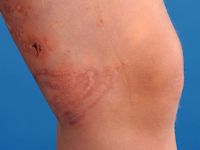

klassieke beeld bestaat uit pijnlijke, lineaire urticariële of vesiculopapuleuze

laesies. Ulceratieve, hemorragische of necrotische laesies zijn echter ook mogelijk.

De laesies ontstaan acuut en zijn binnen een aantal minuten tot uren weer verdwenen.

![Kwallenbeet (click on photo to enlarge) [source: www.huidziekten.nl] Kwallenbeet](../../../images/kwallenbeet-1z.jpg) |

| kwallenbeet |

kwallenbeet |